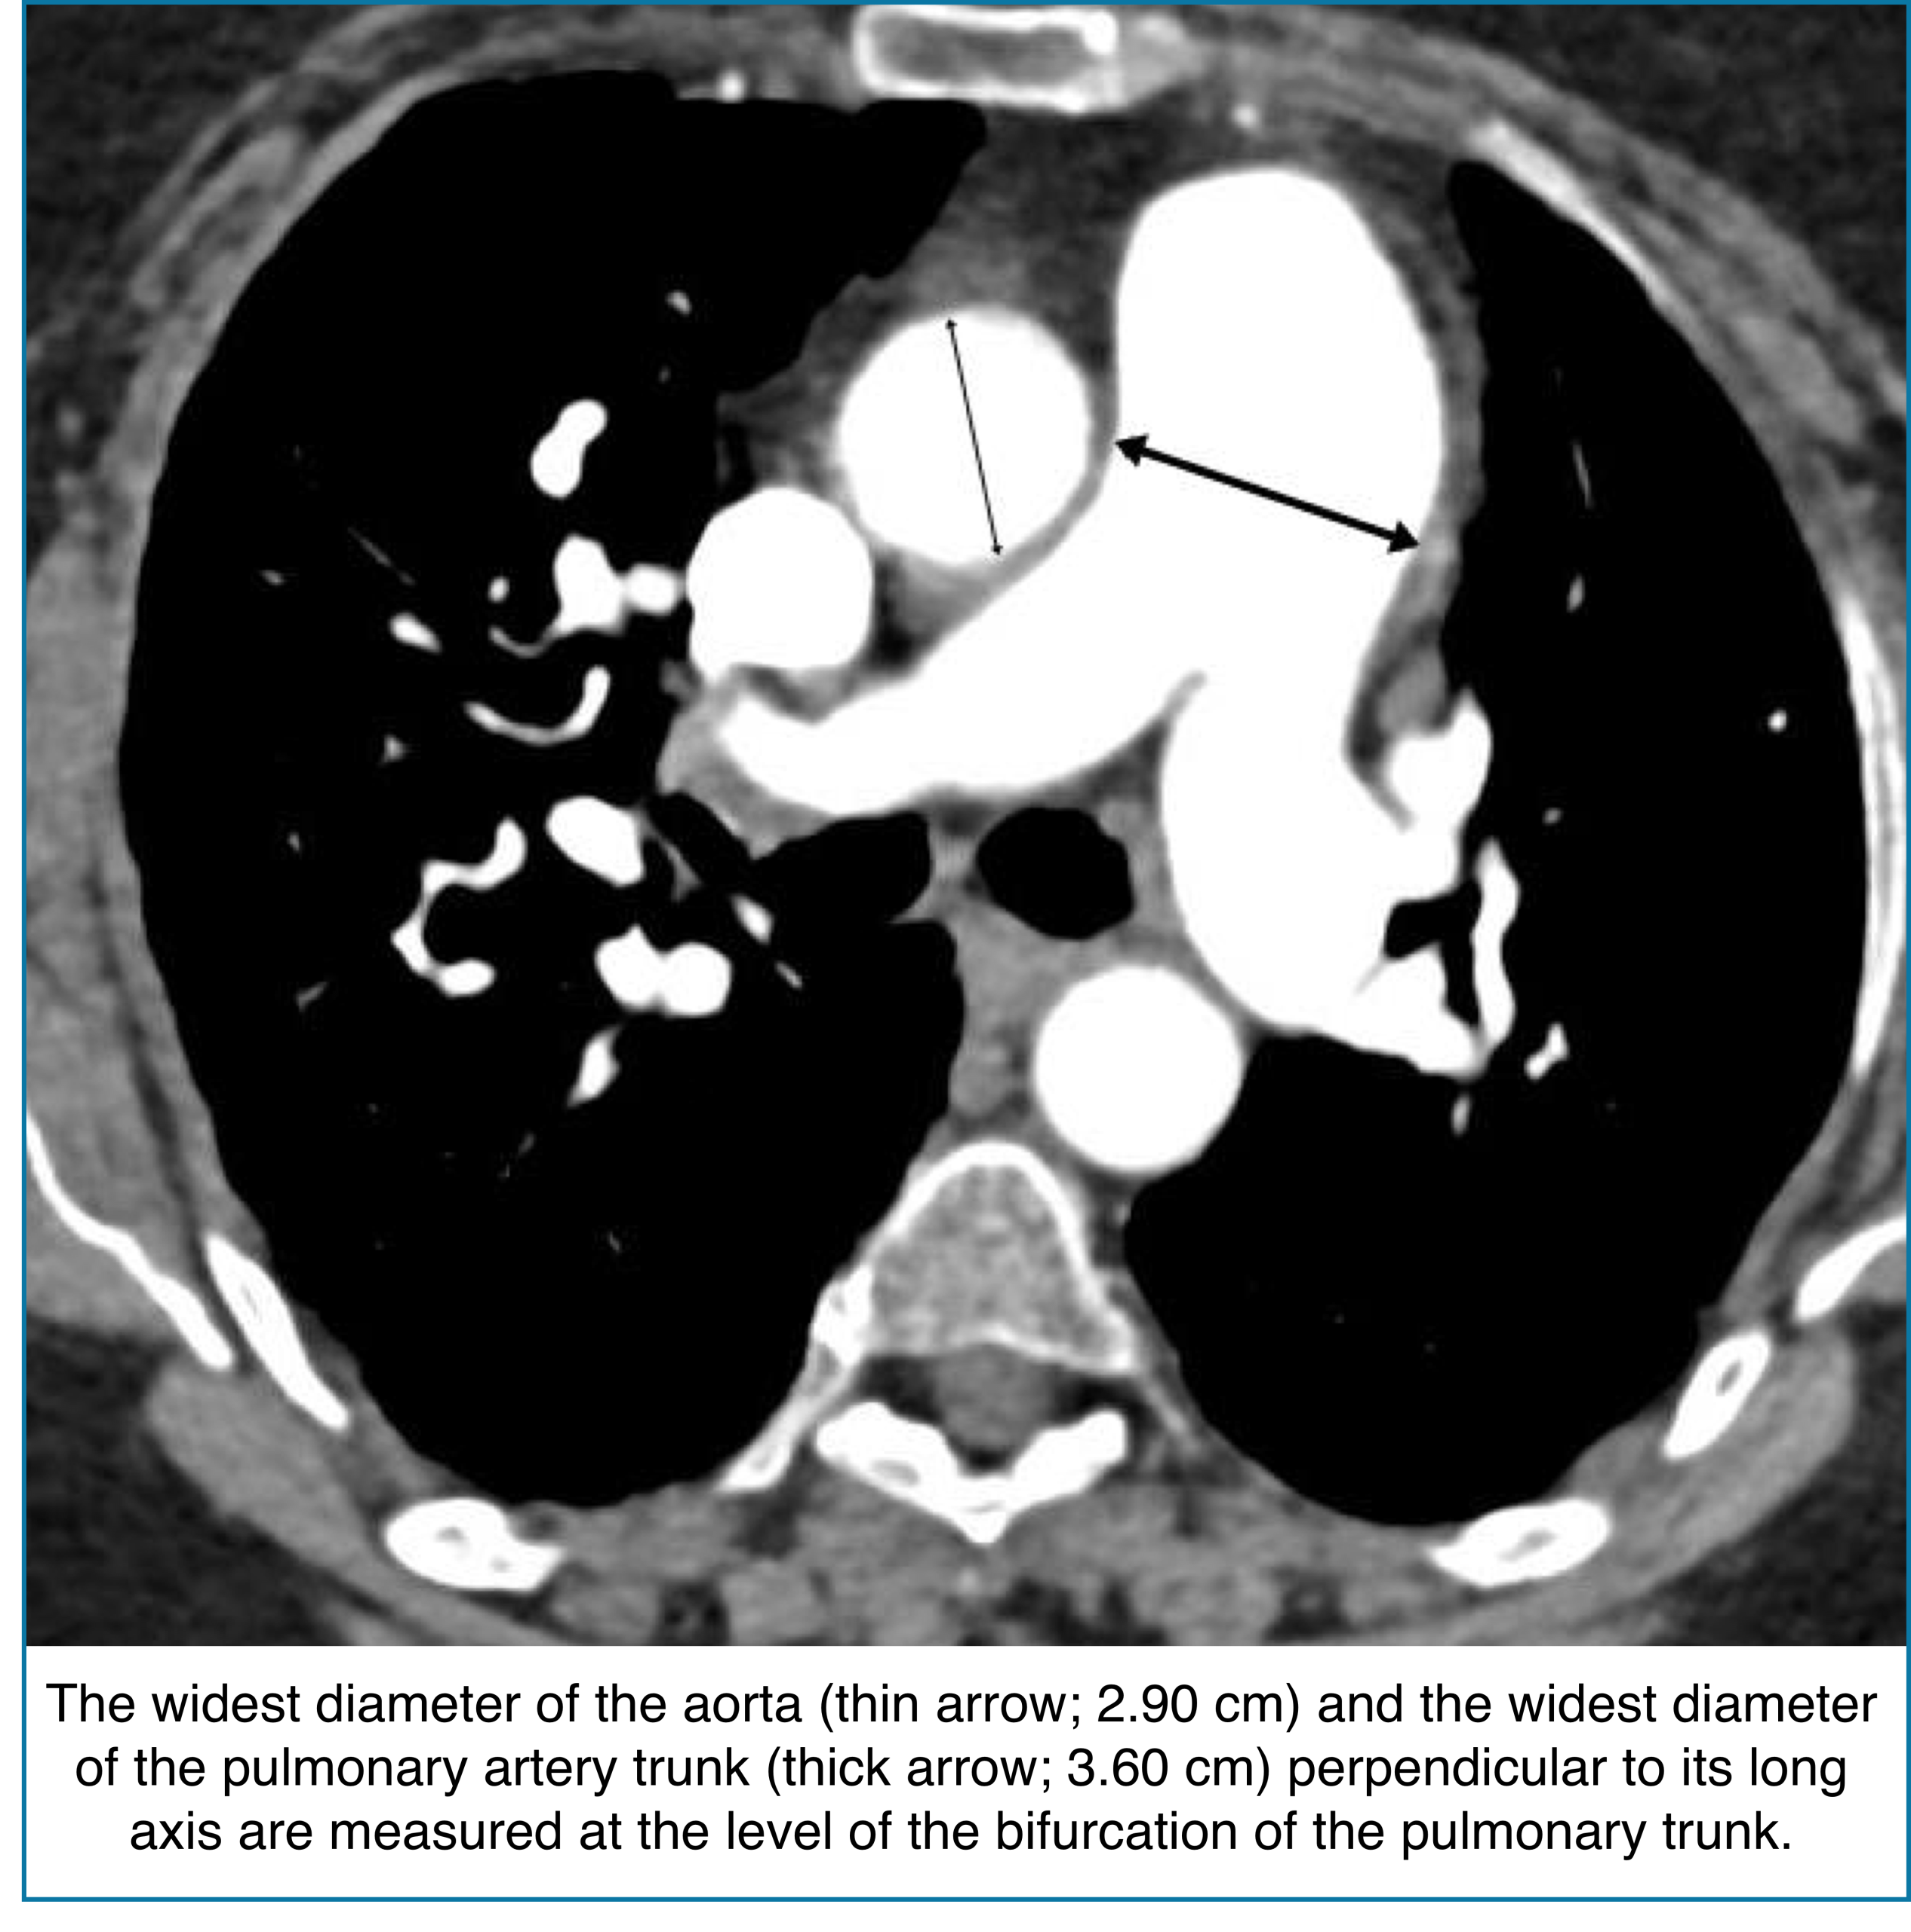

◾️Pulmonary artery dilation

- Pulmonary artery enlargement on CT can signal elevated pulmonary pressures, often reflecting chronicity and severity of pulmonary hypertension. However, it may be absent in acute RV failure, so interpretation must consider the clinical context.

- Key Pearls

- Pulmonary artery)/(aorta) ratio >1.

- This ratio has a fairly high specificity for identifying pulmonary hypertension (~90%).

- The ratio is inaccurate among patients with aortic dilation (more likely in older patients).

- Absolute PA diameter >3 cm → Consistent with PA dilation.

- Specificity may be enhanced by using a cutoff of >32.5 mm.